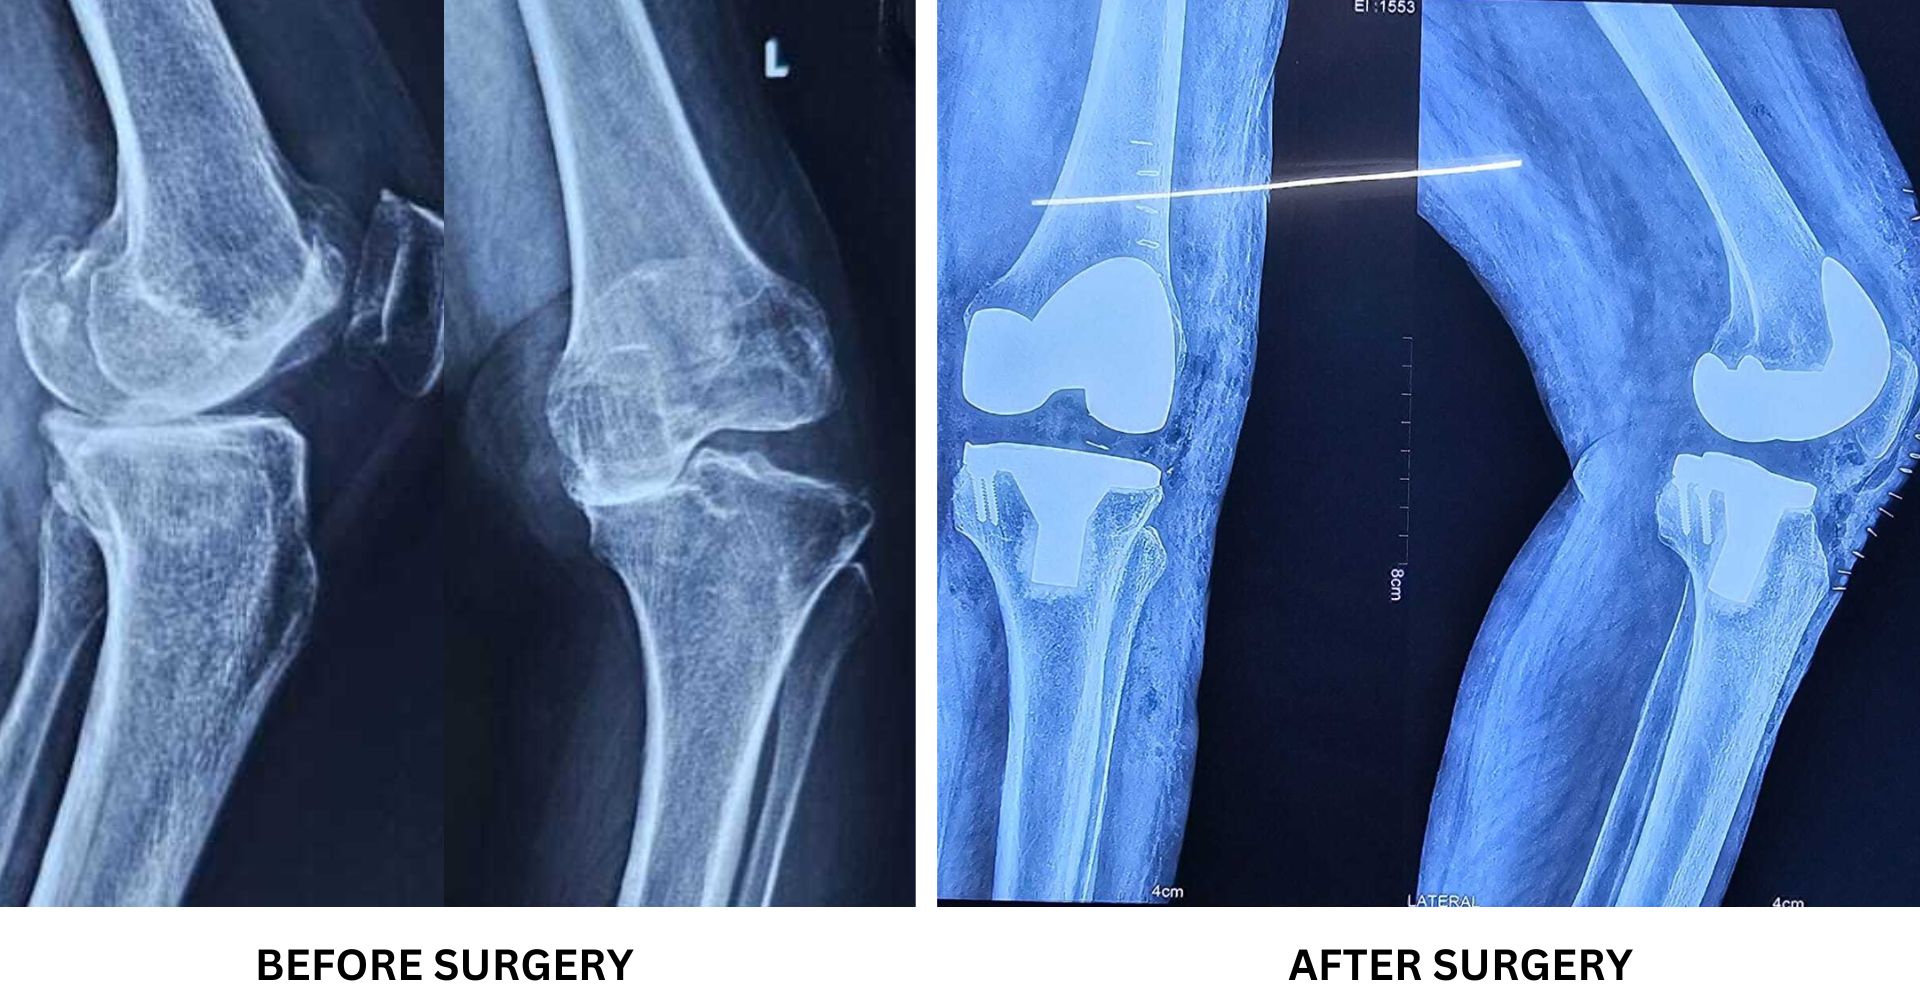

Gallery